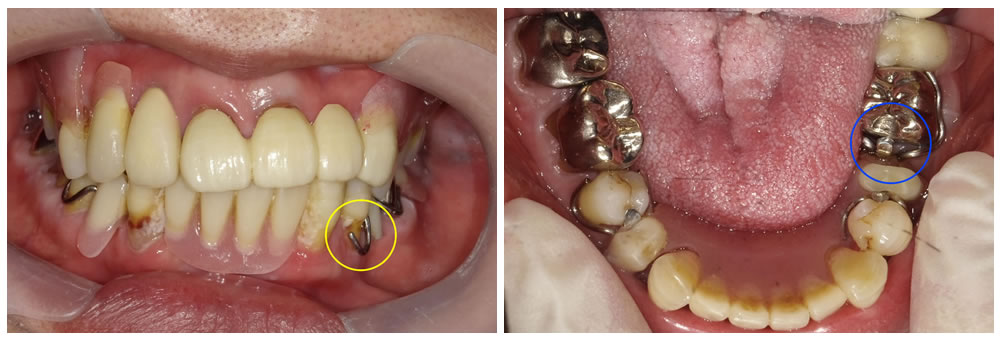

ノンクラスプデンチャーをお口に装着

ノンクラスプデンチャーがお口に入った状態です。金具が無くなったことで、見た目が自然になりました。また、残っている歯にもきれい適合し、入れ歯が安定して話もしやすく、食事の際にも痛みが出なくなったと大変喜んでおられました。今後は入れ歯と残った歯が長持ちするように、入れ歯の調整と歯周病の治療を定期的に行っていくことになりました。